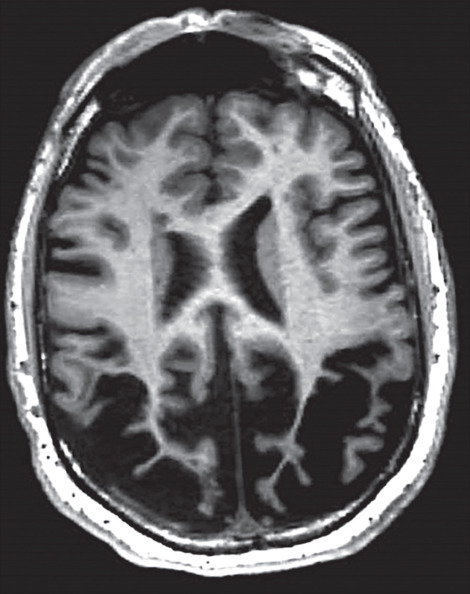

What's the diagnosis? #MedTwitter #FOAMed Dr. Priyam Bordoloi अहिरावण Dr. Shiv_Kumar Dr. Akhil 🇮🇳 Dr. El_Nino